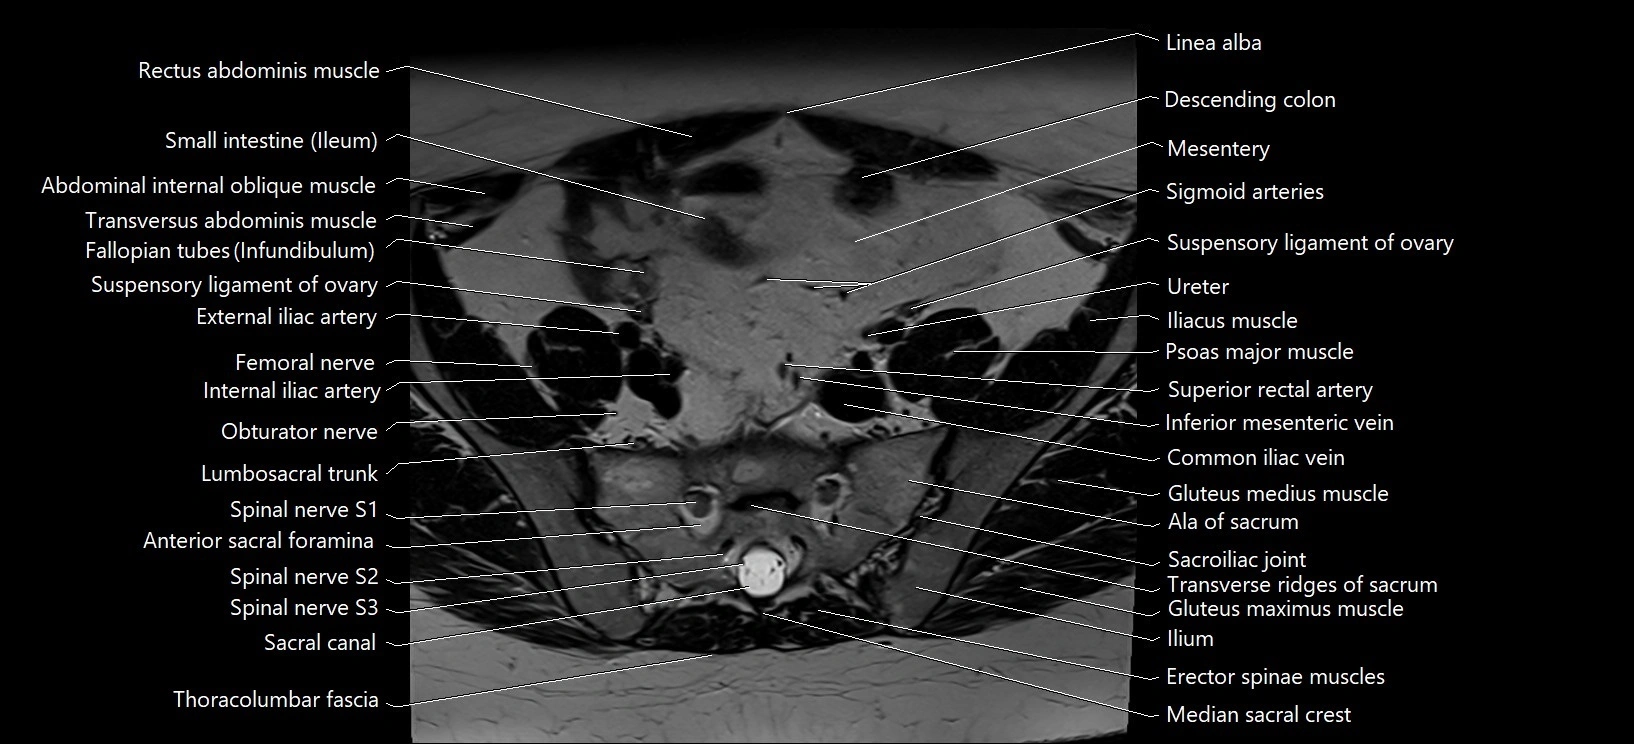

- Ala of sacrum

- Anterior sacral foramina

- Common iliac vein

- Erector spinae muscles

- External iliac artery

- Femoral nerve

- Inferior mesenteric vein

- Internal iliac artery

- Internal iliac vein

- Lumbosacral trunk

- Median sacral crest

- Psoas major muscle

- Sacral canal

- Sacral plexus

- Sacroiliac joint

- Spinal nerve S1

- Spinal nerve S2

- Spinal nerve S3

- Superior rectal artery